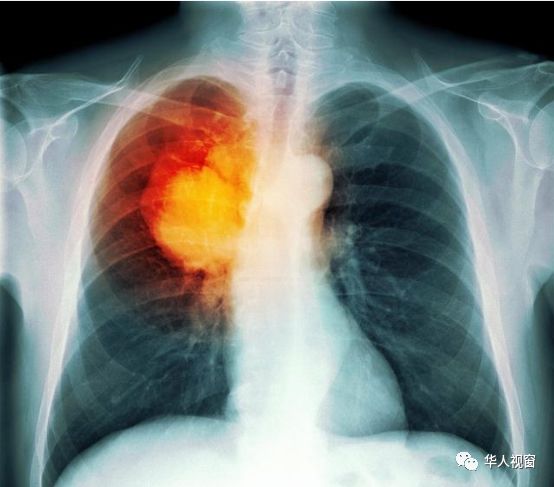

癌症治疗的中国和美国之间是有差距的,但有一些癌症没有区别,如胃癌的5年生存率仅为20%。

在胃癌这方面,无论中国和美国都输了,日本成为最大赢家。

日本胃癌的5年生存率可达80%,并在其他国家倾倒了几条街。